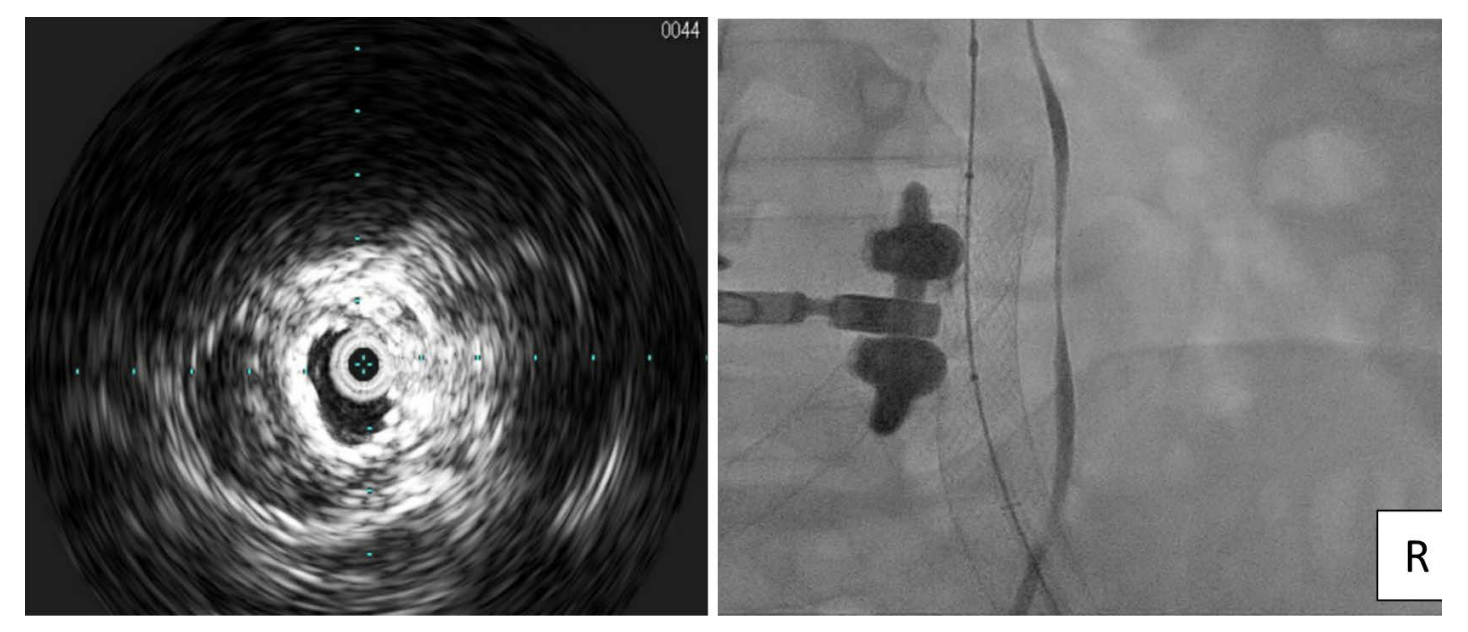

The extensive thrombus in the right CIV was treated with embolectomy using an AngioJet ZelanteDVT thrombectomy catheter (Boston Scientific) after power-pulse spray with tissue plasminogen activator (tPA). Post embolectomy, dilation with an 8 mm Atlas Gold Balloon (BD) at 5 atmospheres (atm) was followed by dilation with a 12 mm Atlas Gold balloon at 4 atm (Figure 3). A 20 x 80 mm WallStent was advanced into the ipsilateral iliac vein and into the IVC adjacent to the previously placed left CIV stent, then post dilated with the 14 mm balloon. The 20 mm diameter of the Wallstent was chosen because the contralateral stent placed in left CIV was measured at 16 mm. IVUS images showed stents adjacent to one another (Figure 4). Popliteal and femoral vein pressure dropped from 48 mmHg at baseline to 18 mm post stenting. Angiography confirmed excellent flow in both the left and right CIV stents (Video 1). The patient was discharged on aspirin and apixaban. At a one-month clinic visit, resolution of pain and swelling had already occurred.